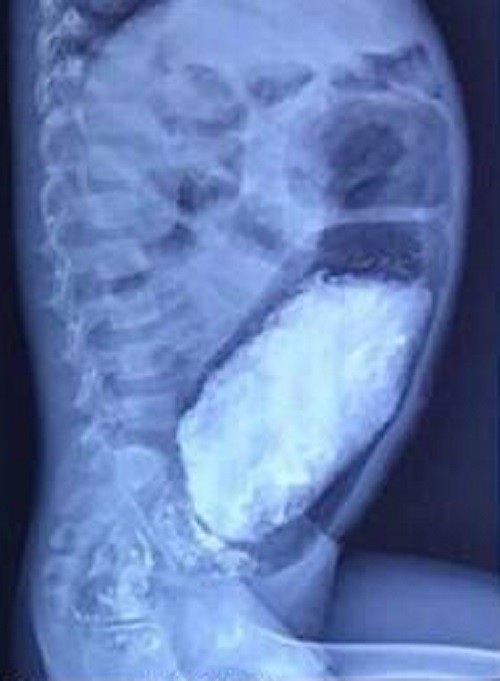

Tại bệnh viện, qua thăm khám và chụp phim, bác sĩ chẩn đoán bé bị hội chứng phình đại tràng bẩm sinh (Hirschsprung), khiến một đoạn đại tràng không có dây thần kinh kiểm soát sự co bóp đại tràng. Sau hội chẩn bác sĩ quyết định phẫu thuật cho bệnh nhi. Sau 3 giờ khẩn trương trên bàn mổ, bác sĩ đã cắt bỏ phần trực tràng bị phình dài gần 20cm, dãn to 20cm, cùng gần 3 kg phân ứ đọng bên trong. Sau phẫu thuật, bé đã ăn uống và tự đi cầu được, tình trạng táo bón không tái phát.